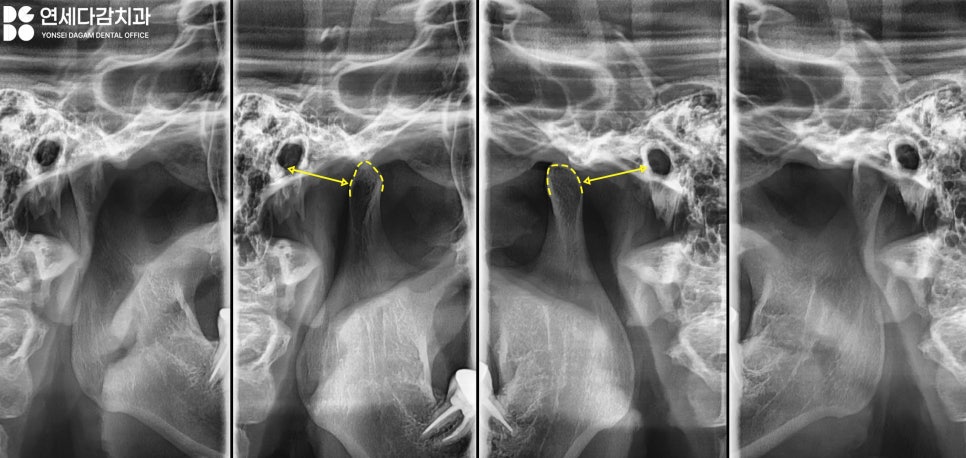

그리고 손가락 세 개를 붙여

개구량 검사를 실시한 결과,

개구제한이 생겨 실제로 손가락이

두 개 정도밖에 들어가지

않을 정도였습니다.

정상적인 경우 세 개 정도가

들어가야 하는 4~5cm에 비하면

낮은 수치였죠.